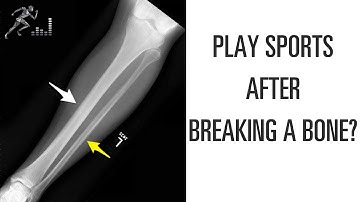

Return to sports after a tibia fracture